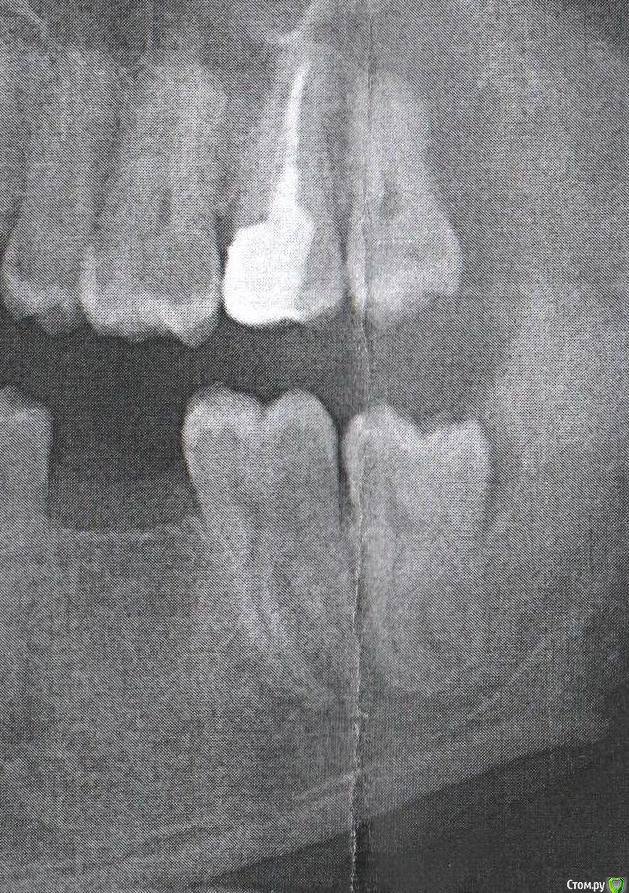

Wise Опубликовано 24 июля, 2015 Поделиться Опубликовано 24 июля, 2015 Здравствуйте, Что делать с зубом мудрости? Левый нижний. Под ним и/или рядом с ним уже третий раз, за последние 2 месяца, что то восполяется, щека опухает, изнутри ничего не видно, ощутимый бугорок, пью ципролет, хирург надрезал капюшон. Кто-что говорит, конечно хотелось бы оставить. Поделитесь мнениями из практики, если снимка достаточно? Заранее благодарен! Ссылка на комментарий

AlexanderGudkov Опубликовано 24 июля, 2015 Поделиться Опубликовано 24 июля, 2015 Удалить верхний и нижний. 6ой протезировать 2 Ссылка на комментарий

Yana guapa Опубликовано 25 июля, 2015 Поделиться Опубликовано 25 июля, 2015 Здравствуйте, Что делать с зубом мудрости? Левый нижний. Под ним и/или рядом с ним уже третий раз, за последние 2 месяца, что то восполяется, щека опухает, изнутри ничего не видно, ощутимый бугорок, пью ципролет, хирург надрезал капюшон. Кто-что говорит, конечно хотелось бы оставить. Поделитесь мнениями из практики, если снимка достаточно? Заранее благодарен! причем удалять надо и нижний и верхний (над ним). так как когда нижнего не станет , верхний начнет опускаться вниз и пойдут проблемы с суставом. - "природа не терпит пустоты" Ссылка на комментарий